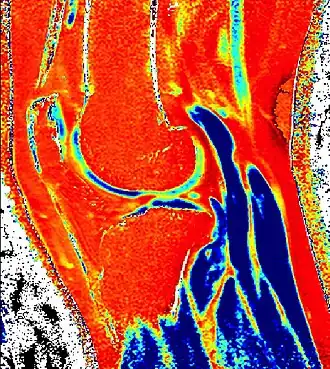

![]() dGEMRIC T1 Map of knee cartilage | |

| Purpose | measures relative proteoglycan content of articular cartilage |

Delayed gadolinium-enhanced magnetic resonance imaging of cartilage or dGEMRIC measures the fixed-charge density and relative proteoglycan content of articular cartilage using the spin-lattice relaxation time or T1 relaxation time.[1] Current research is investigating the clinical application of dGEMRIC as a quantitative tool for monitoring cartilage function in diseased or repair cartilage.[2]